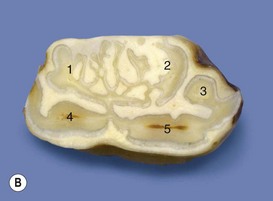

Fig. 8.20 (A) The caudal root of this dysplastic, apically infected mandibular CT is absent, and its site has a large apical opening leading into a wide necrotic pulp chamber (arrow). Some extraction-induced loss of periodontal membrane has occurred. (B) The occlusal surface shows an additional dysplastic pulp chamber (surrounded by a ring of enamel) that is occlusally exposed.

(From Dacre et al,26 with permission from The Veterinary Journal.)